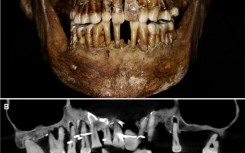

The teeth of 17th century French aristocrat Anne d'Alegre, with a gold wire threading through several

French aristocrat's golden dental secret revealed 400 years on